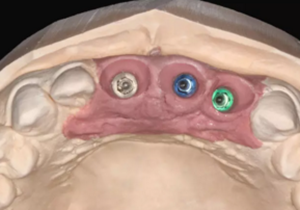

(2)即刻種植、即刻臨時修復(fù)。術(shù)中不翻瓣微創(chuàng)拔除牙根,牙槽 窩骨壁完整。在多級導(dǎo)板輔助下完成種植窩洞制備,植入Bego柱形種植 體,型號分別為:上頜右側(cè)中切牙位點4.1mm×15mm、上頜左側(cè)中切牙 位點?3.75mm×15mm、上頜左側(cè)側(cè)切牙位點3.25mm×15mm,扭矩均為 35N·cm。種植體與唇側(cè)骨壁間隙約2mm,植入Bio-Oss®Collagen骨膠 原。戴入橋用鈦臨時基臺,臨時冠就位順利,自凝樹脂口內(nèi)粘接后適當(dāng)修整 外形,充分磨光,調(diào) 至正中 、前伸 和側(cè)方 與對頜牙均無接觸。術(shù)后 根尖片顯示種植體位置、方向良好。

圖9 植入種植體

圖10 植入骨膠原

圖11 戴入臨時修復(fù)體

圖12 即刻修復(fù)完成

圖13 術(shù)后即刻根尖片